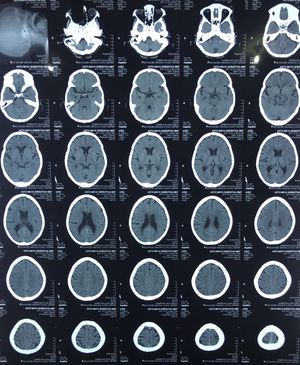

cT head trauma

RTA no loc or any other symptoms and signs

Trauma

Neuro

Cthead